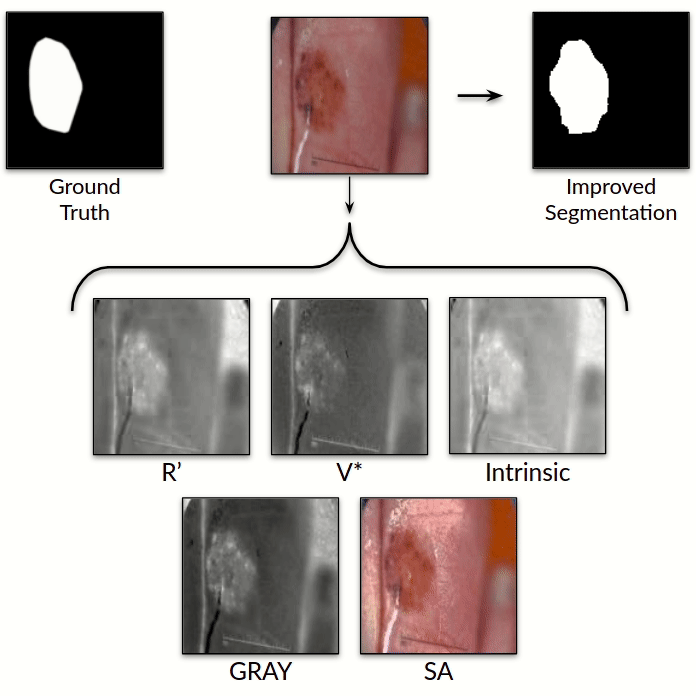

Illumination-based Transformations Improve Skin Lesion Segmentation in Dermoscopic Images

Kumar Abhishek, Ghassan Hamarneh, Mark S. Drew

ISIC Skin Image Analysis Workshop, IEEE International Conference on Computer Vision and Pattern Recognition (CVPR), 2020 We incorporate information from specific color bands, illumination invariant grayscale images, and shading-attenuated images obtained from RGB dermoscopic images of skin lesions to improve the lesion segmentation. [Abstract] [BibTeX] [Presentation Slides]

The semantic segmentation of skin lesions is an important and common initial task in the computer aided diagnosis of dermoscopic images. Although deep learning-based approaches have considerably improved the segmentation accuracy, there is still room for improvement by addressing the major challenges, such as variations in lesion shape, size, color and varying levels of contrast. In this work, we propose the first deep semantic segmentation framework for dermoscopic images which incorporates, along with the original RGB images, information extracted using the physics of skin illumination and imaging. In particular, we incorporate information from specific color bands, illumination invariant grayscale images, and shading-attenuated images. We evaluate our method on three datasets: the ISBI ISIC 2017 Skin Lesion Segmentation Challenge dataset, the DermoFit Image Library, and the PH2 dataset and observe improvements of 12.02%, 4.30%, and 8.86% respectively in the mean Jaccard index over a baseline model trained only with RGB images.